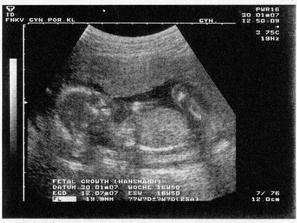

Honzíček 2.7.2007

Podle ultrazvuku ve 20.tt by to měl být chlapeček.

Nakonec přišel Honzíček na svět už 2.7. 2007 v 11:15 císařským řezem. Měřil 50 cm a vážil 3320 g.